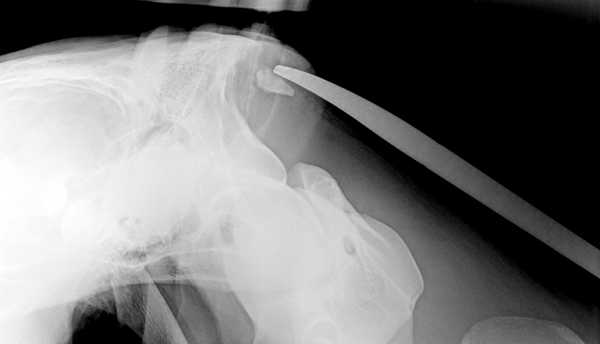

- Orthopädische Eingriffe

aller Art - Arthroskopische Eingriffe

- C Bogen Operationen

- Osteosynthese